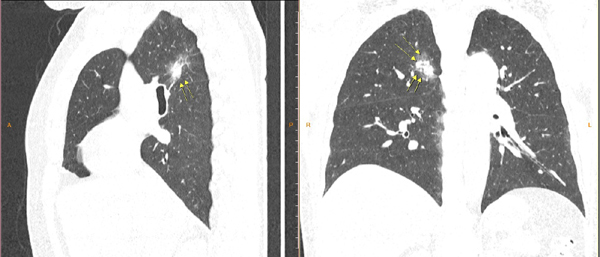

So với độ tuổi thì các chỉ số xét nghiệm của bệnh nhân N.T.N đều nằm trong ngưỡng cho phép, tuy nhiên, trên phim chụp cắt lớp vi tính phát hiện một khối u nhỏ chỉ 7mm trong phổi - nghi ngờ có nhiều đặc điểm ác tính. Bệnh nhân đã được sinh thiết và có kết quả ung thư phổi giai đoạn đầu.

| Hình ảnh khối u phổi được phát hiện qua chụp CT 128 dãy tại MEDLATEC |